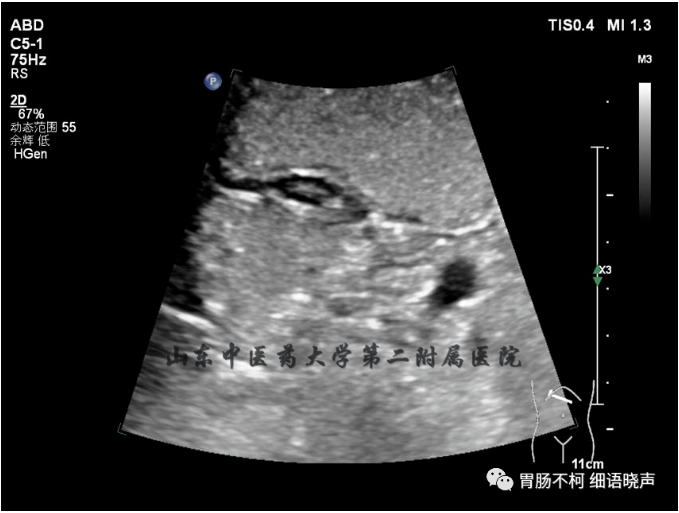

病例四:(此病例由昌乐中医院超声科、山东中医药大学第二附属医院胃充盈超声精品培训班优秀学员高志勇、张海成大夫提供、在山东胃肠超人2019一群请我会诊的病例)

胃窦部固有肌层来源、不规则囊性区外连着扁盘状网格状实性回声的病灶,诊断实性部分为异位胰腺,囊性部分为异位胰腺发生炎症后形成的假性囊肿。病人有餐后相应部位疼痛的症状。